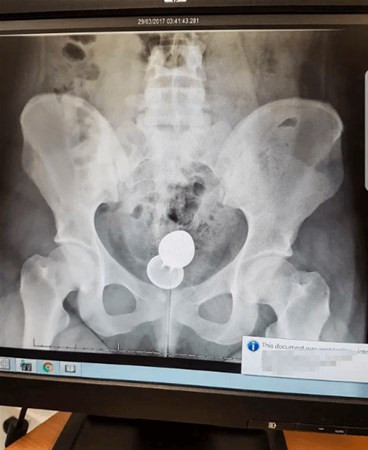

İNGİLTERE'de Batı Sussex’te yaşayan 20 yaşındaki Emily Georgia sevgilisi ile yaşadığı cinsel ilişki sırasında sevgilisinin bir cinsel ilişki oyuncağı anüsünden geçerek bağırsaklarına gitti. Bakın akılalmaz olayın devamında neler oldu.

Bunun üzerine panik olan çift paslanmaz çelikten yapılmış oyuncağı çıkarmayı denedi. Ancak her seferinde daha da içeriye gitmesine neden oldu. Defalarca çıkarmayı deneyen çift daha sonra pes etti ama Emily'nin içi rahat değildi.

Emily doğal yolla çıkarmayı defalarca denemesine rağmen bunu başaramadı. Erkek arkadaşı ertesi gün herşeyin düzeleceğini ve kendiliğinden çıkacağını ileri sürdü. Ancak ertesi günde çıkmayan cisim yüzünden panik olan Emily durumu ev arkadaşına haber verdi.

Ev arkadaşı hemen doktora gitmelerini söylemesine rağmen durumdan çok utanan Emily zorla da olsa hastaneye gitmeye ikna oldu.Hastanede durumundan bahseden Emily Georgia’ya hemen gerekli tetkikler yapıldı. Çekilen röntgen filminde olayın boyutlarının çok tehlikeli olduğunu fark eden doktorlar durumu Emily’e anlattılar.